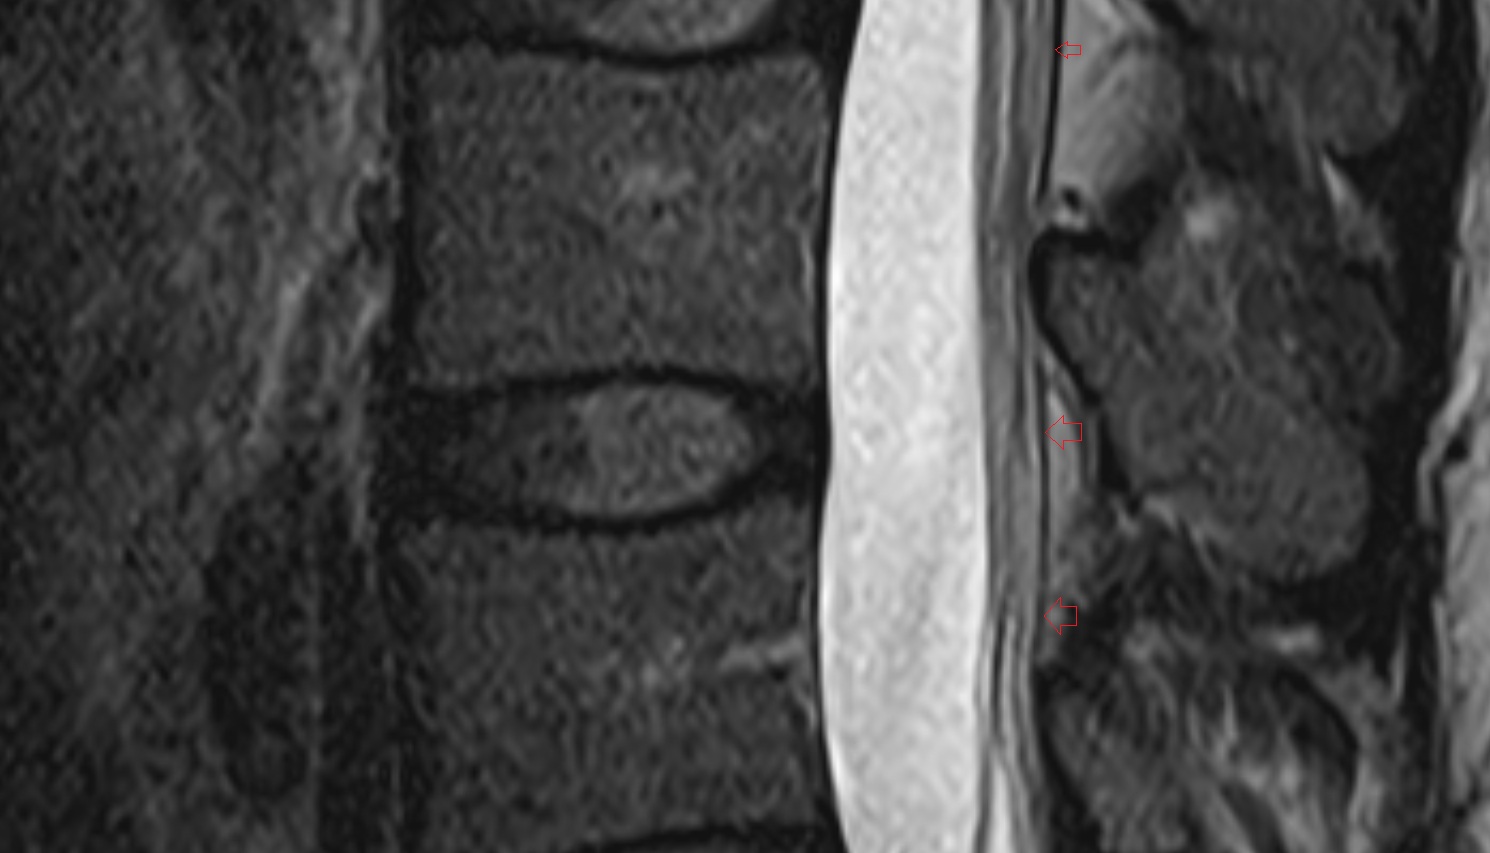

- Cauda equina

- Conus medullaris

- Traversing nerve root of spinal nerve

- Exiting nerve root of spinal nerve

- Spinal dura mater

- Spinal epidural space

- Dorsal traversing nerve root

- Ventral traversing nerve root

- Dorsal exiting nerve root

- Ventral exiting nerve root

- Dorsal root ganglion of spinal nerve